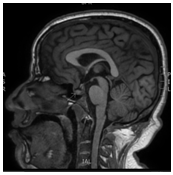

A 31years old man presented to the emergency department with five days history of severe headache accompanied by nausea, dizziness, and blurred vision. The patient’s past medical history was unremarkable and was not on any medications. He is married with 3children, the youngest is 3years old. On physical exam, he was hemodynamically stable with no orthostasis, conscious, oriented and in moderate pain distress (5/10 on pain scale chart). His central nervous system exam showed normal mini-mental status, cranial nerves examination was normal with preserved visual fields. His presentation prompted a brain MRI which showed pituitary macroadenoma with a suprasellar extension (Figure 1) with hemorrhage suggestive of pituitary apoplexy. Hormonal profiles is shown in Table 1, consistent with panhypopituitarism due to non-functional pituitary macro-adenoma with apoplexy. The decision for conservative management was opted for in keeping with the severity of the presentation. He improved and discharged 2days later on hydrocortisone and levothyroxine. However, a few days later he expressed a major concern of diminished libido and sexual dysfunction. At this point, Cabergoline 0.5mg orally twice weekly (off-label) was started with an improvement in his sexual functions within a few days, recovering his pituitary functions (off hormonal replacement). Follow-up MRIs (Figure 2) showed marked shrinkage of the macroadenoma which completely resolved in the most recent image (Figure 3) two years later.

Figure 2 Marked shrinkage of the macroadenoma